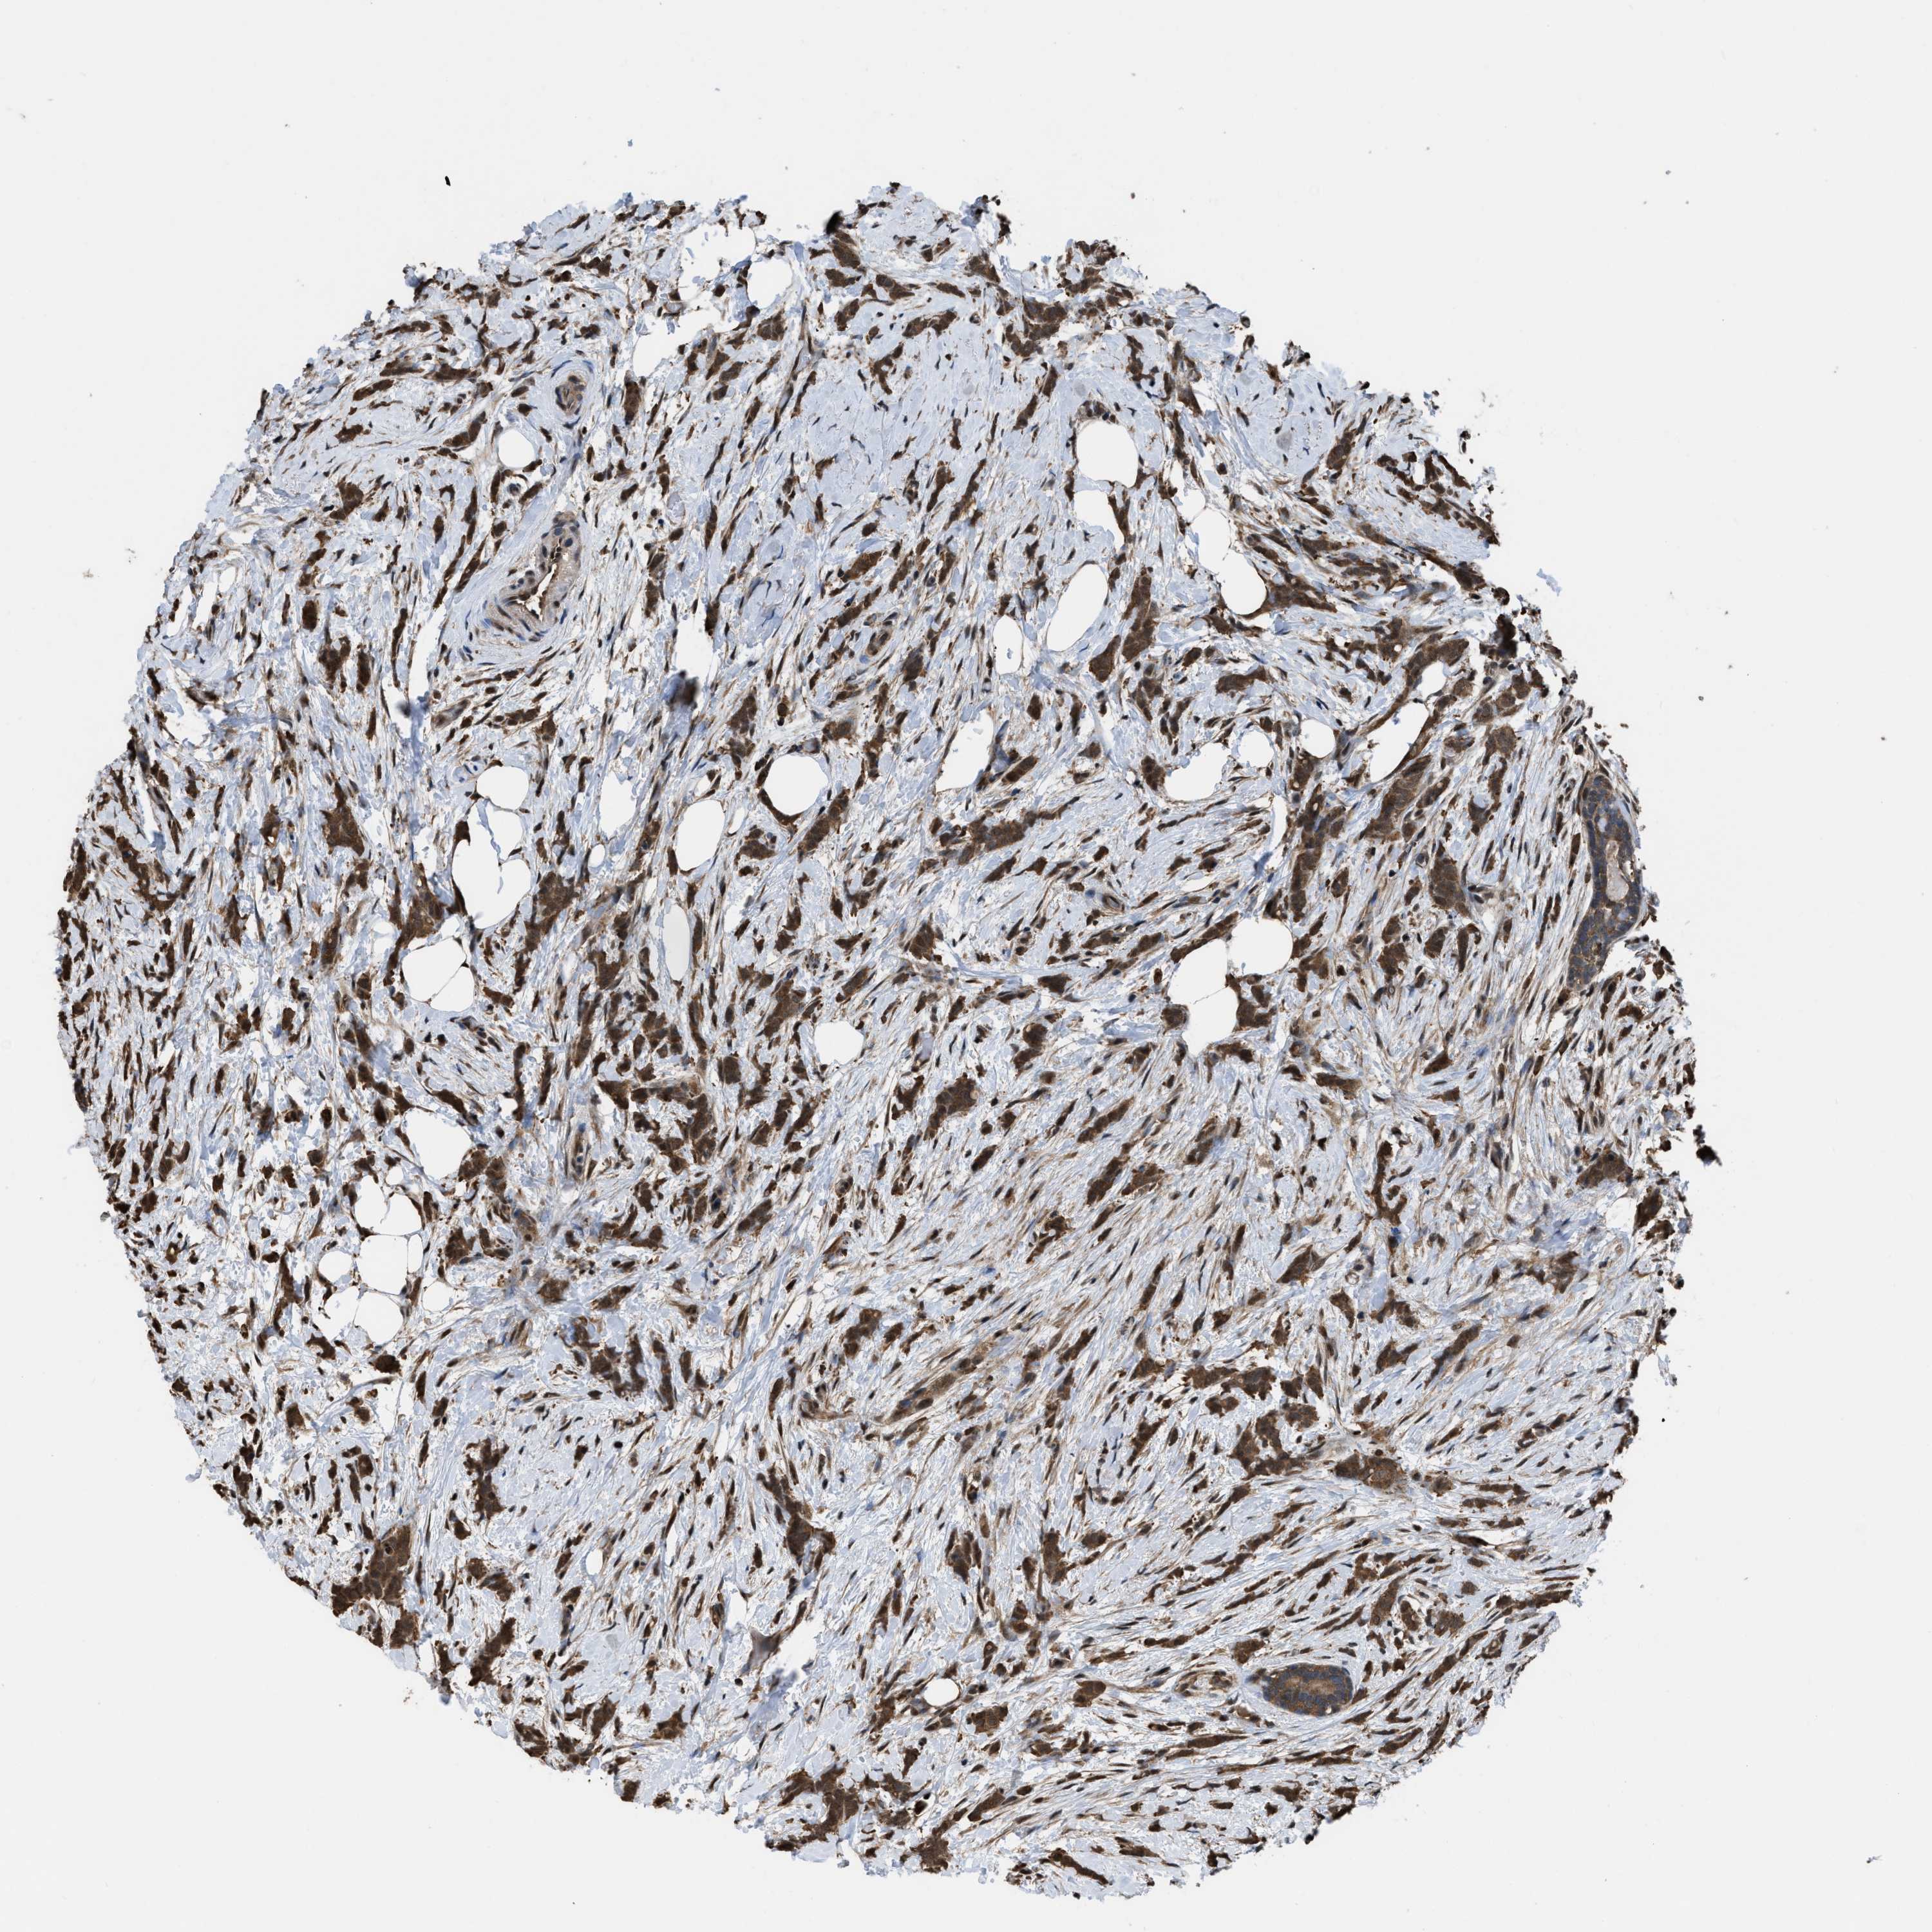

CANCER BREAST CANCER Show tissue menu

BRCA TCGA BRCA VALIDATION PROTEIN EXPRESSION

ANTIBODIES